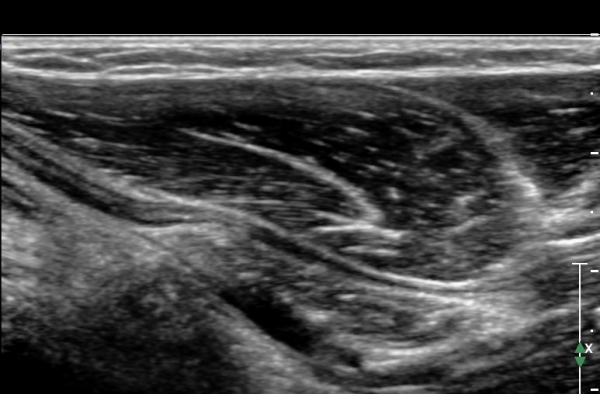

ÃÊÀ½ÆÄ °Ë»ç : ȸ³»±Ù ±ÙÀ§ºÎ¿¡¼­ Á¤Á߽Űæ Ⱦ´Ü¸é°Å»ç¿¡¼­ ƯÀÌ ¼Ò°ßÀ» º¸ÀÌÁö ¾ÊÀ¸³ª(»çÁø 1) ȸ³»±Ù ¿ä°ñµÎ ±â½ÃºÎ

¿¡¼­  Á¤Á߽ŰæÀÇ ±¹°íÀû ¾Ð¹Ú ¹× ÆíÆòÈ­°¡ °üÂûµÊ(»çÁø 2). ÀÌ·± º¯È­´Â °ÇÃø(»çÁø 5)°ú ºñ±³Çϸé

¶Ñ·ÇÇÔ.